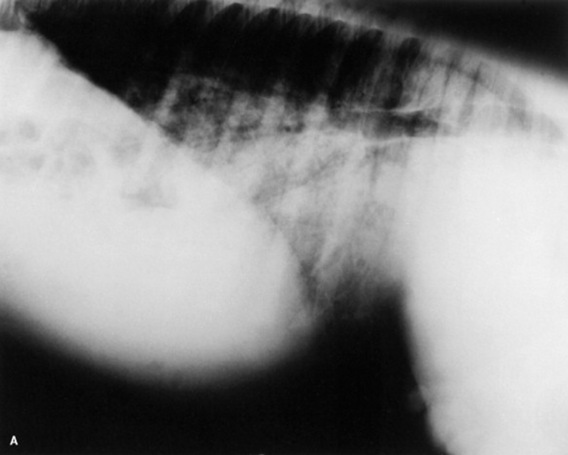

Skeletal maturity is assessed by radiographing a carpus and a tarsus for evidence of incomplete ossification (Fig. 19-1). Accelerated ossification does not appear to be a feature of foals born prematurely after exposure to chronic in utero stress. Incomplete ossification coupled with periarticular laxity predisposes the premature or dysmature foal to long-term skeletal problems. Foals with incomplete ossification and more than 30% reduction of the central and/or third tarsal bones with pinching or fragmentation of the dorsal aspects of affected bones commonly develop degenerative joint disease and have a guarded prognosis for future athletic performance. Restriction of exercise is recommended in order to minimize collapse of developing carpal or tarsal bones, but forced recumbency may predispose the foal to or exacerbate pulmonary disease. Furthermore, normal load bearing encourages ossification. Periarticular laxity predisposes the premature foal to angular limb deformities that facilitate abnormal load bearing and increase the risk of cuboidal bone crush injury of the carpus or hock. Splinting and attention to hoof care are recommended if angular limb deviation develops. In most cases flexural deformities and laxities improve over time. Dorsal splints are recommended for flexural deformities involving the fetlock, and heel extensions are helpful to foals with flexural laxity.

Fig. 19-1 A, Lateral tarsus of a 1-day-old, 305-day gestational age colt. Note the lack of ossification of the small tarsal bones. B, Lateral tarsus of the same foal as in A, at 3 weeks of age, showing irregular ossification. Without the initial radiograph, increasing ossification could have been confused with bone lysis and osteomyelitis. The foal is reported to be sound at 6 months of age.